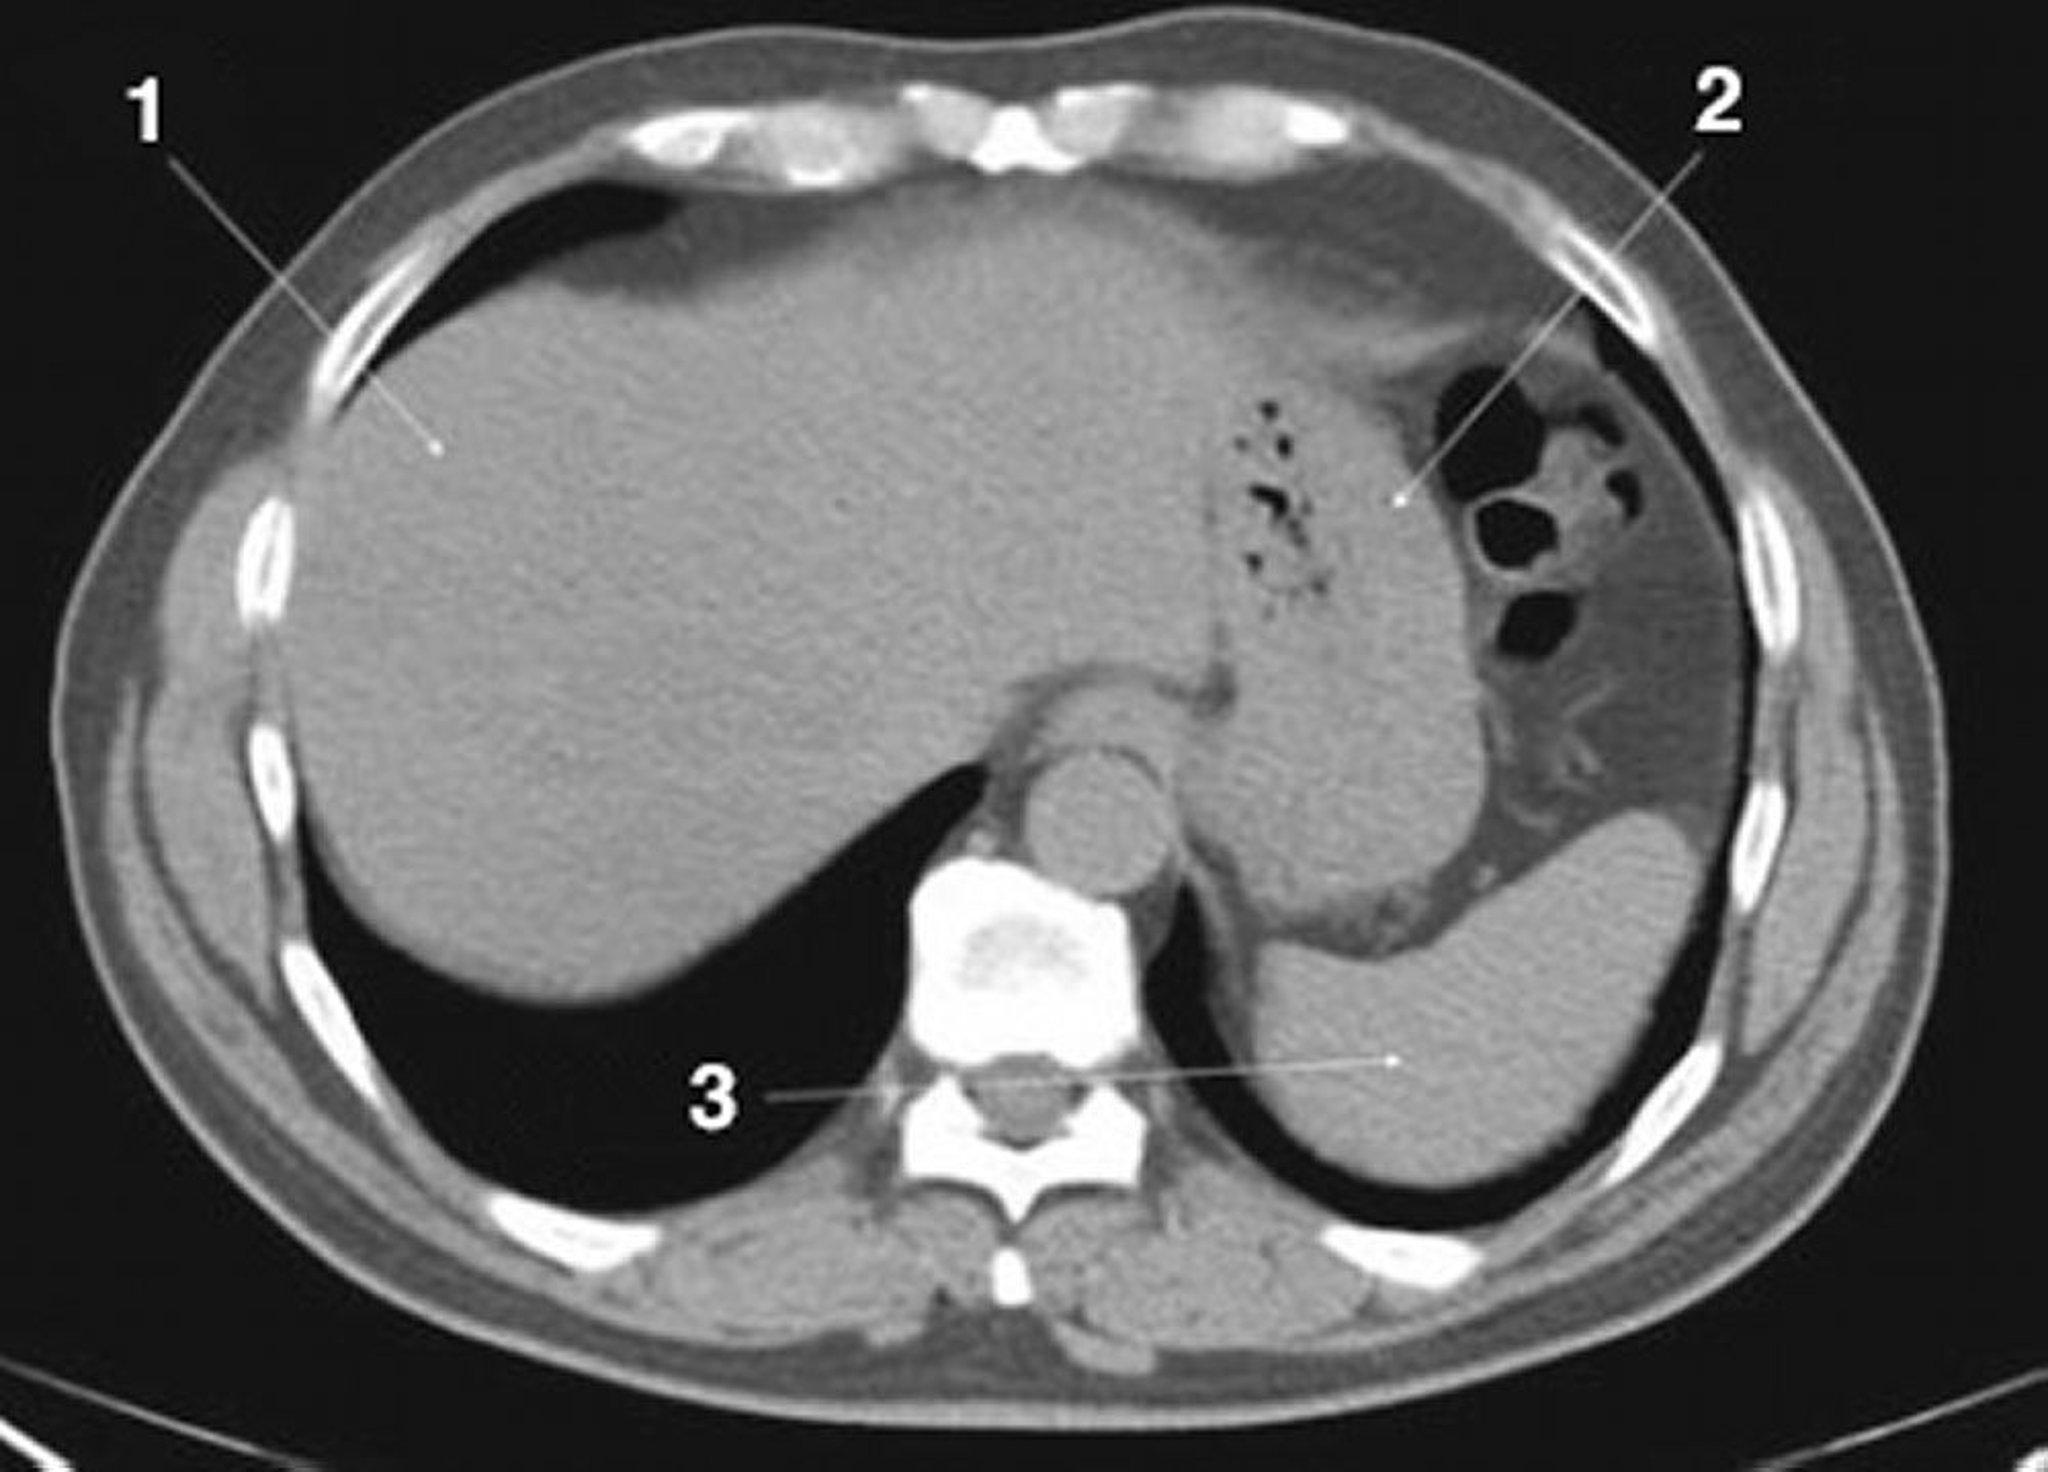

正常解剖を示した腹部および骨盤の単純CT画像(スライド3)

1 = 肝臓;2 = 胃;3 = 脾臓。